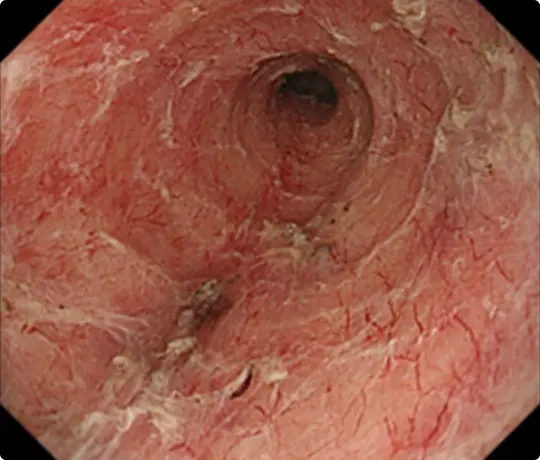

全周性の食道がんに対するESDです。

がんの範囲を分かりやすくするため、食道にヨード染色を行っています。ピンク色に見えるところに食道がんがあります(食道の全周を占めています)。

病変の周りに目印のため、電気メスで白いマークを付けています。

粘膜の下に液体を注入して病変を浮かせます。

病変の外側を電気メスで切開したところ。

粘膜の下の組織(粘膜下層)を電気メスで剥がしているところです。

全周性のESD後です。穿孔(壁に穴があくこと)などの問題なく、病変を切除しました。切除後は潰瘍が出来ますが、1~2ヵ月で治ります。

食道は元々細いため、大きな病変を切除した後は、潰瘍の治癒に伴い食道がより細くなり、ご飯が通らなくなる場合があります。近年、ステロイドの注射で細くなるのを予防出来ることが分かって来ました。

当科でも広範な食道ESD後はステロイドを注射し、食道が細くなるのを予防しています。